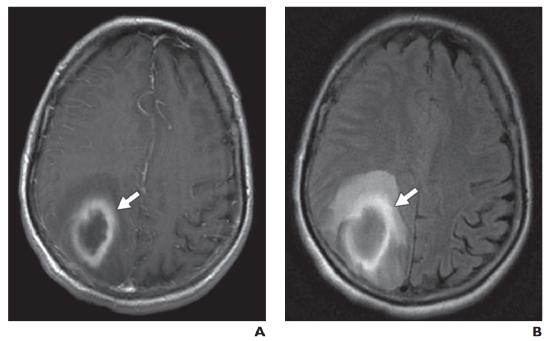

图15—后部可逆性脑病综合征。A,未增强的头颅CT显示枕叶后部低密度(箭头),主要是血管源性的,尽管有皮质受累的病灶区。B,FLAIR MR图像再次显示对称性高信号(箭头),同时累及白质和灰质。C,对比增强T1加权磁共振成像显示在这个区域有微弱的脑回状强化(箭头),被认为是继发于高血压引起的短暂血管扩张和血脑屏障的破坏。

脑部感染可能由细菌引起,或者病毒、菌类、和其他致病因素引起,例如朊病毒。影像学表现包括脓肿、脑膜炎、脑室炎和脑炎。炎症原因包括脱髓鞘疾病(多发性硬化症、后部可逆性脑病综合征(图15A ), 15B, 和15C)、进行性多灶性脑白质病)、血管炎、自身免疫综合征、癫痫、偏头痛、辐射(图16A )和16B), 和药物反应。这些病变由于血脑屏障的损伤而产生血管源性水肿。内部扩散受限区域也可能存在,并且可能表示蛋白质或出血性内容物(通常在 T1 加权成像上呈高信号)或伴有细胞毒性水肿的缺血(在 T2 加权成像上呈高信号,在 T1 加权成像上呈低信号)。对比增强在急性期最为强烈,并随时间推移而减弱。在脑部感染的情况下,不均匀性软组织强化提示蜂窝织炎,而具有致密边缘强化的机化液体则与脓肿有关(图17A )和17B)。